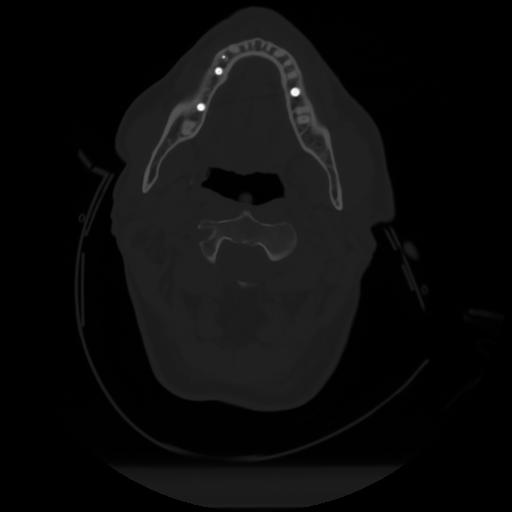

10 P.BLANDAS,,Axial,2.0,P.BLANDAS,,